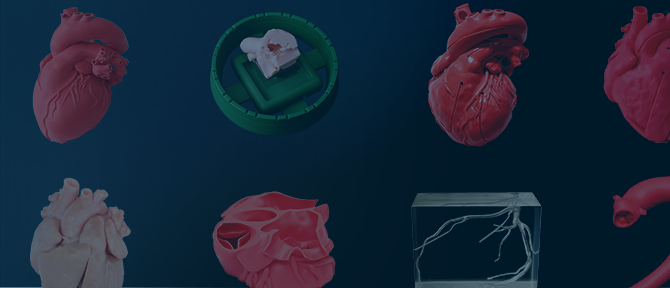

活用領域の拡大

エコーの使用が可能で目的に応じて濃淡の調節も可能。

ウレタンやシリコン製のモデルと組み合わせることで、幅広い領域での活用を実現。